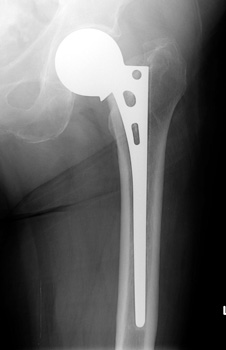

• Unipolar hemiarthroplasty

• no longer used in USA

Unipolar hemiarthroplasty.